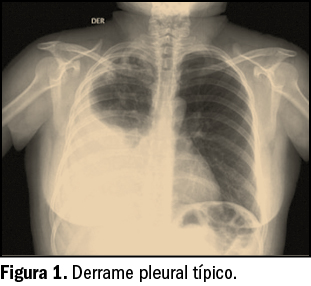

De las seis especies comprendidas en este género, solo son potencialmente patógenas Listeria monocytogenes y L. ivanovii, afectando esta última principalmente a los animales, por lo que L. monocytogenes (Figura 1) –debido fundamentalmente a su gran resistencia en condiciones poco favorables– es la única implicada en la patología humana conocida como listeriosis. Las otras cuatro, L. innocua, L. seeligeri, L. welshimeri y L. grayi (sin. murrayi) son inocuas para el ser humano y para los animales (Montville et al., 2005).